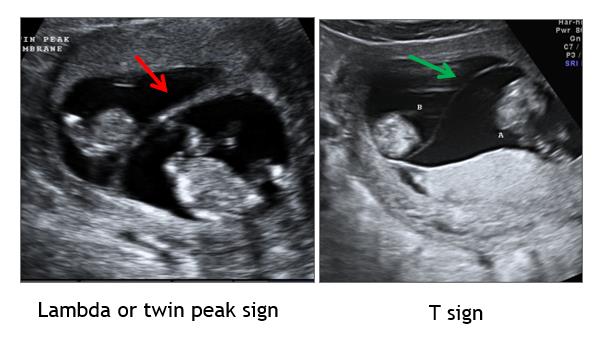

Several guiding principles are used to define chorionicity including membrane thickness, number of membrane layers, number of placental sites, presence of the lambda or T-sign, and other composite measures; (Figure 2) and (Figure 3). Composite measures would include ability to discern the number of placental masses, number of gestational sacs, number of fetal poles, and whether fetal sex is concordant/discordant. The number of yolk sacs usually equates to the number of amnions. Membrane thickness in monochorionic (MC) pairs has been described subjectively as “thin” or “whispy”; this description has been investigated using numerical measurement with thresholds for thickness ranging from <1.0-2.0 mm [18-20].

Figure 3. First Trimester membranes and sonographic markers.